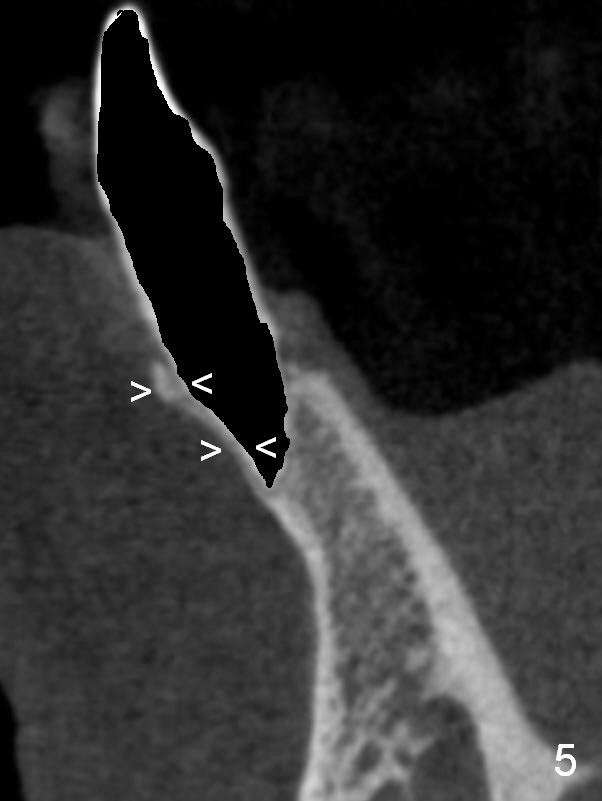

A 74-year-old man has several missing teeth (Fig.1). His 1st goal is to replace the lower left lateral incisor (Fig.2). The residual root has an apical lesion (Fig.3 *). To describe intraop findings, a CT image of a different patient is used (Fig.4 coronal section; B: buccal; L: lingual). After extraction, the buccal plate is found to be thin and low (Fig.5 arrowheads). A 1.5 mm pilot drill (Fig.6 red line) is used to initiate osteotomy in the lingual plate of the socket. Once the drill penetrates the lingual plate, the trajectory changes and the depth is 17 mm from the gingival margin (Fig.7). A PA is taken (Fig.8); it appears that the osteotomy can be extended more apically. When the pilot drill extends to 20 mm, there is sudden empty feeling. The lingual plate has perforated (Fig.9). A new osteotomy is established buccally (Fig.10 pink). To avoid buccal plate perforation, especially in the buccal undercut area (>), the coronal end of the drill has to be tilted buccally (<--). An angled abutment (3x20 mm, 15°) is placed (Fig.11,12). The abutment is modified (Fig.13,14) to accommodate an immediate provisional (Fig.15,16 P). Perio dressing is to be applied to prevent the bone graft from getting dislodged buccally (Fig.15). The dressing is in place 7 days postop (Fig.17).